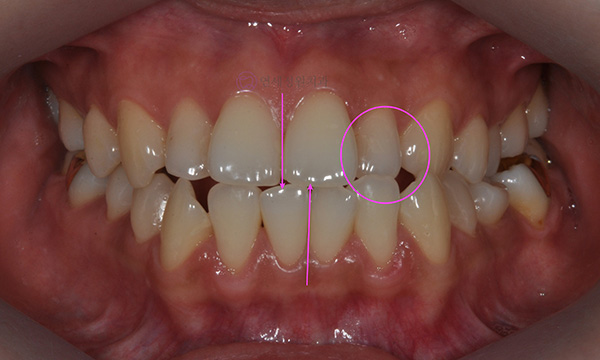

위 환자분은 치아 중심선이 맞지 않는다는 주소로 치과에 내원하셨습니다. 미소시 사진을 보면 위 치아도 오른쪽(사진 상 왼쪽)으로 틀어져 있고, 아래 치아도 왼쪽(사진 상 오른쪽)으로 틀어져 있었습니다. 그리고 양쪽 입꼬리 근육의 활성도도 차이가 있어서, 웃었을 때 왼쪽 입꼬리가 오른쪽보다 덜 올라가서 비대칭이 더 강조되어 보였습니다.

2020.7

치아 중심선의 차이를 개선하고, 얼굴의 중심과 치열의 중심을 맞춰주기 위하여 오른쪽 아래 작은 어금니를 하나만 발치하여 그 공간으로 아래 치열을 오른쪽으로 돌려주고, 위 치열은 전체적으로 왼쪽으로 치열을 이동시켜서 중심선을 맞추어 주었습니다.